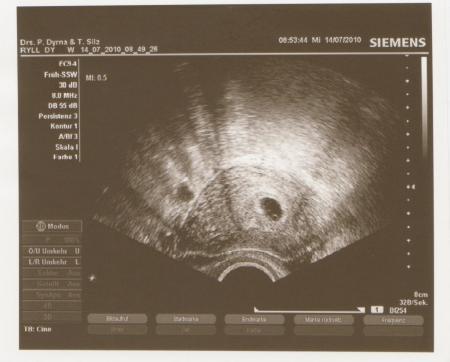

Die Fruchthöhle mit einem Punkt

...also es ist nun der 16.08. geworden, 9tage früher. Immerhin

da bin ich dann in der 10.ssw